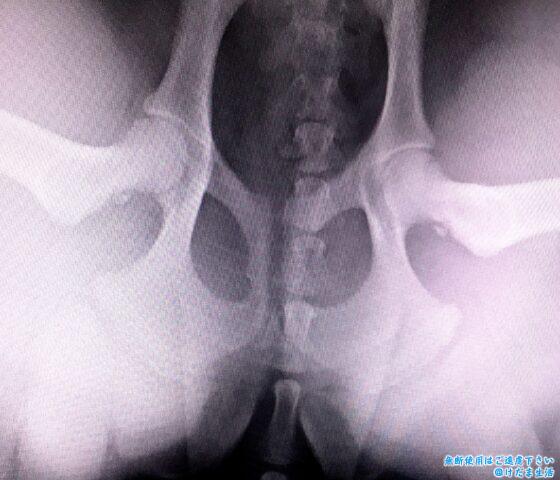

普通の仰向けの姿勢と、

足を器具で広げた状態。

寛骨臼から大腿骨頭が外れているのが分かります。